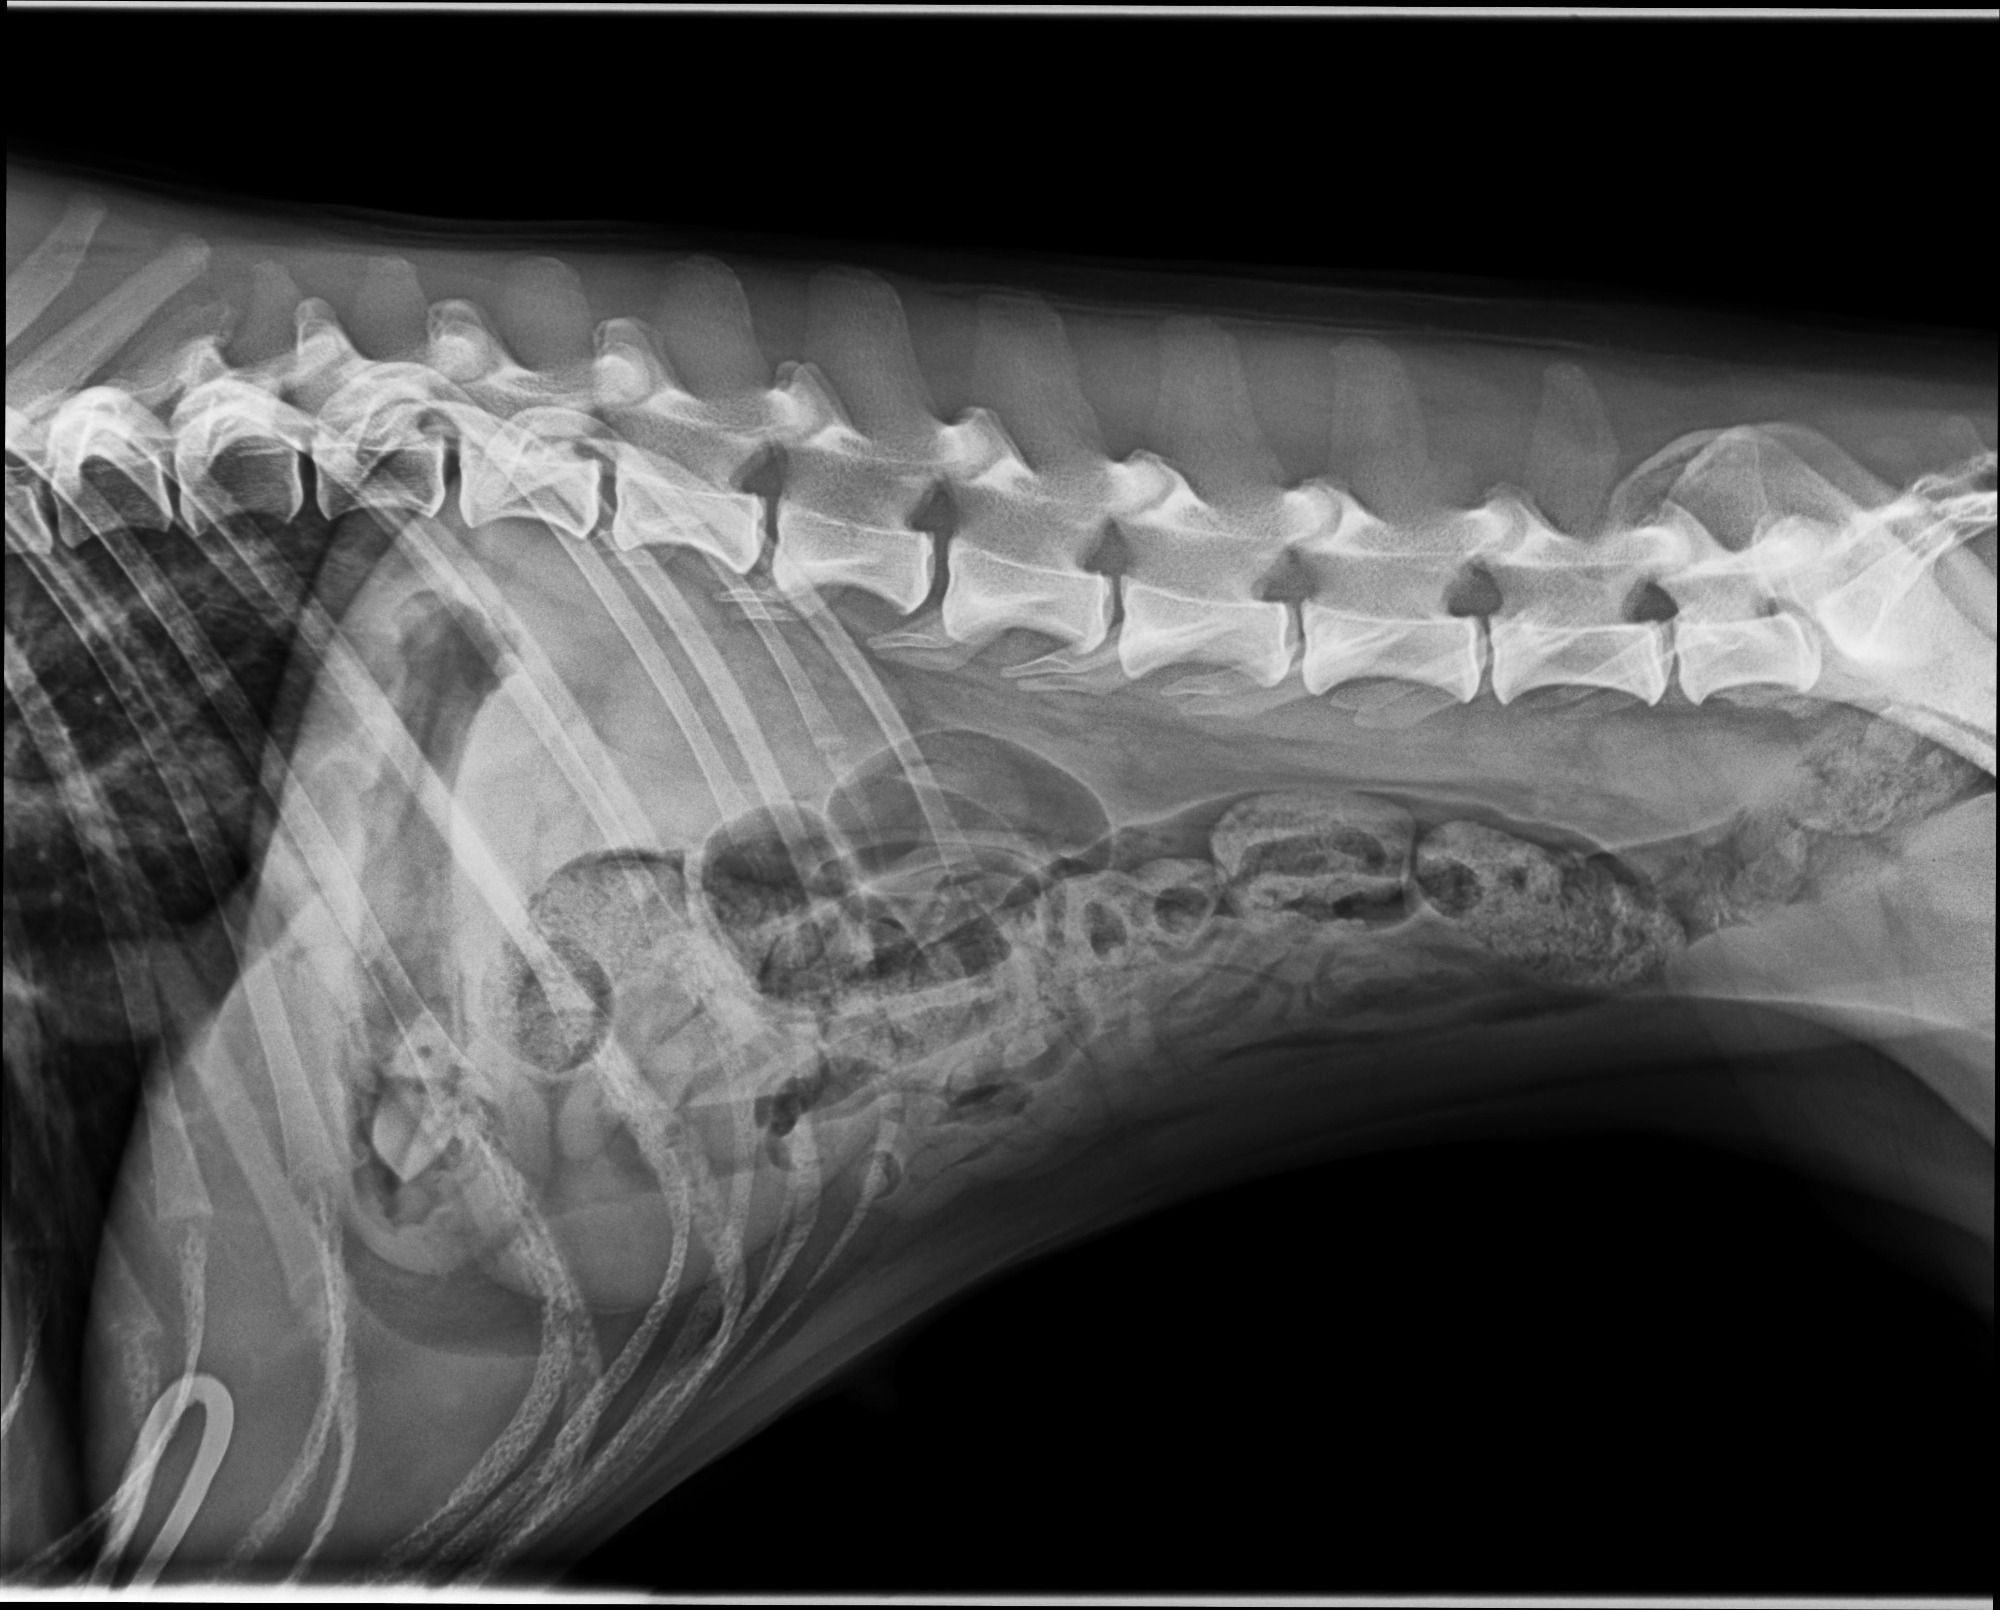

Striptease van Sapho´s Hoeve

*13.08.2019

Lightning VSH X Playfull VSH

Herz 0

HD B

Spondy 0